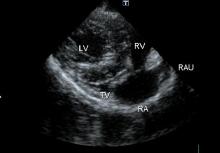

●心尖四腔断面

@僧帽弁における逆流、流入血流速の観察、測定

A三尖弁における逆流、流入血流速の観察、測定

B各心筋、各腔の観察

●僧帽弁にカラーを乗せて逆流を観察。